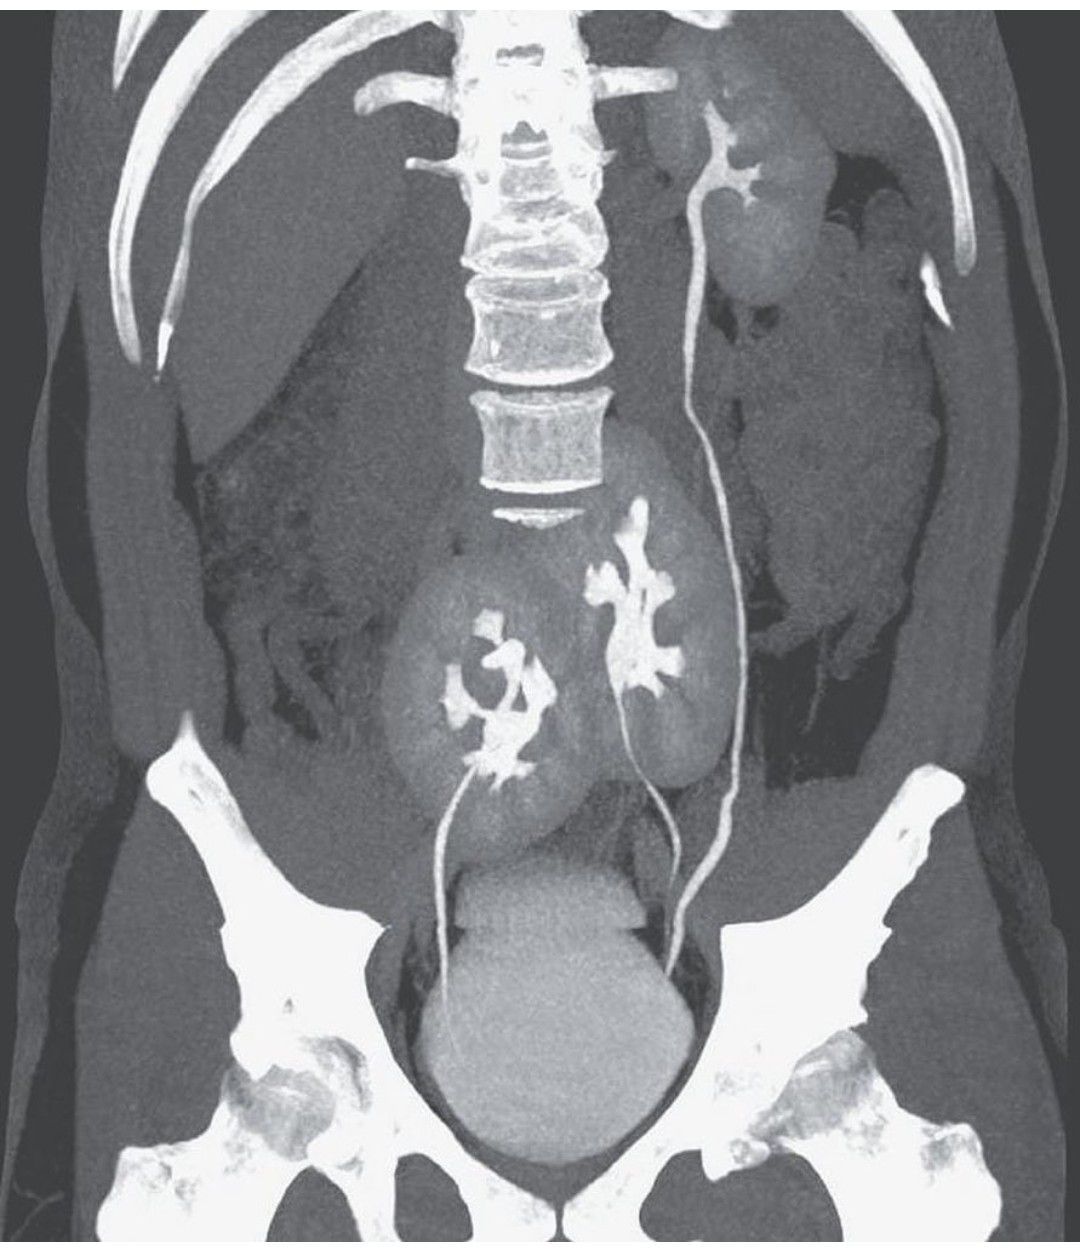

A Brazilian man discovered he has a third kidney after going to the doctor with severe low back pain. A man presented to the outpatient clinic with severe low back pain. As part of the evaluation, computed tomography (CT) was performed. The scan incidentally showed the presence of three kidneys: a normal-appearing left kidney and two fused kidneys in the pelvis. The ureter from the left pelvic kidney joined the ureter from the other left kidney just above its entrance into the bladder. The ureter from the right pelvic kidney entered the bladder on the right side. The CT scan also showed a herniated disk between L4 and L5. Renal function was normal, with a creatinine level of 0.9 mg per deciliter (80 μmol per liter) (normal range, 0.6 to 1.0 mg per deciliter [53 to 88 μmol per liter]). This uncommon congenital abnormality was thought to be the consequence of aberrant processes during embryogenesis. The duplicate left kidney may have resulted from a premature division of the left ureteral bud. In addition, the right and lower left developing kidneys fused and did not ascend during development. Affected persons are commonly asymptomatic, and as in this case, the condition may not become known until imaging is performed for another reason. The patient’s back pain was attributed to the lumbar disk herniation, and he was treated with an oral analgesic agent. Photo Credit: The New England Journal of Medicine Reference: https://www.nejm.org